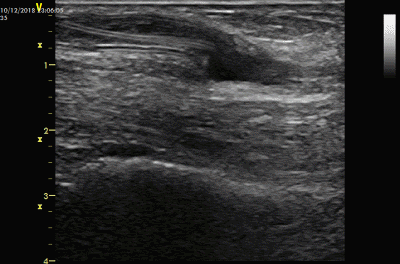

经过这样的溶栓,血栓可以发生以下一些变化

部分血栓溶解成液体

部分大块血栓裂解成小块血栓

血栓变得松软

血栓当中出现一条“通道”,这是由于导管经过时的挤压和溶栓作用产生的

部分血栓溶解成液体,部分大块血栓裂解成小块血栓

经过溶栓,有的AVG血流恢复较好,有的则恢复较弱血流,也有的血流仍然未恢复。